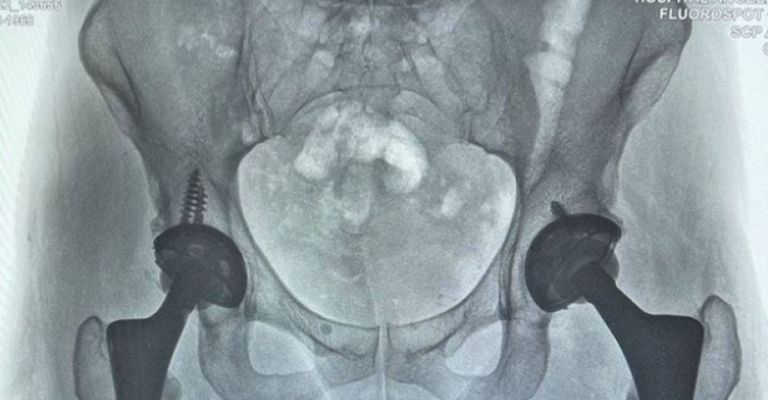

Ciudad de México.-Luego de que la cantante mexicana,Alejandra Guzmánsufriera un accidente arriba del escenario, por medio de redes sociales compartió una fotografía, en la cual exhibe las dos prótesis de la cadera, esto tras ser víctima de una negligencia médica durante el año 2009, misma que provocó otros problemas que se activaron en el 2013.

Tras esa mala práctica médica, larockerafue sometida a al menos 41 cirugías, en la cuales buscaban que volviera a caminar de forma normal, además del desgaste que ha tenido por su larga trayectoria como bailarina, por lo que en los últimos años se ha cuidado dicha zona, pues cabe mencionar que dicho procedimiento estético pudo haberle costado la vida.

Fue en el 2016, cuando a ‘La Guzmán‘ le colocaron otra prótesis, a lo cual ella se burló al menciona que sería una Alejandra biónica, sin embargo, a partir de ese procedimiento, ella ya no presentó más problema, sino hasta seis años después tuvo un inconveniente en un escenario de Washignton, esto luego de que se encontraba en un concierto.

En su publicación, la intérprete deVolverte a Amar, textualizó “Todo en su lugar”, a lo cual de inmediato no faltaron los buenos deseos de los fans, así como de alguno amigos del medio del espectáculo, tales como Pati Chapoy, Montserrat Olivier, Dunia Ojeda, Fey, Ángela Aguilar, entre otras personalidades.